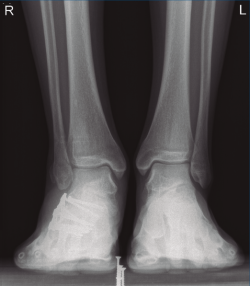

Figura 1. Luxación del astrágalo en mortaja tibioperonea, fractura maléolo peroneo y espacio subperoneo ocupado por calcáneo.

Se trata de un varón de 19 años que ingresa en reanimación tras precipitarse desde una altura de aproximadamente 10 metros. El paciente presenta una fractura estallido de L3 con afectación del canal medular junto con una fractura del vértice inferior de L4, así como una fractura luxación de calcáneo, asociada a una fractura del maléolo peroneo y del maléolo tibial posterior (Figuras 1 a 6) diagnosticadas mediante TC total body (por eso no se dispone de radiografías simples al momento del ingreso). Como podemos comprobar, se trata de una fractura de doble trazo de tipo hundimiento/depresión de la carilla articular (Figuras 5 y 6).

Figura 8. Radiografía anteroposterior de tobillo, inclinación lateral del astrágalo, ocupación del espacio subperoneo, fractura maléolo peroneo y apertura de sindesmosis.

Figura 13. Radiografía anteroposterior de ambos tobillos a los 9 meses de la cirugía.